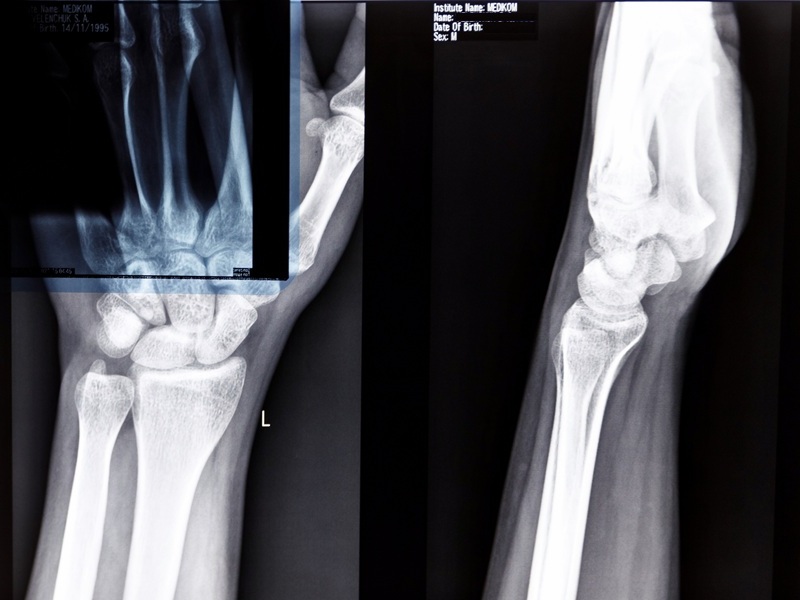

Висока анатомічна деталізація променево-зап'ясткового суглоба за допомогою МРТ

Променево-зап'ястковий суглоб — вразлива ділянка тіла. При травмуванні зап’ястку будь-які рухи кистями, що часто повторюються у побуті, викликають біль. Обмеження рухливості верхньої кінцівки через хворобу чи больовий синдром знижує якість життя. Точно оцінити стан суглоба та призначити ефективне лікування допомагає МРТ зап'ястя. Бажаєте пройти таке дослідження на якісному обладнанні і під контролем висококваліфікованих лікарів? Звертайтеся до Клініки МЕДІКОМ у Києві, щоб оперативно отримати точні результати діагностики.